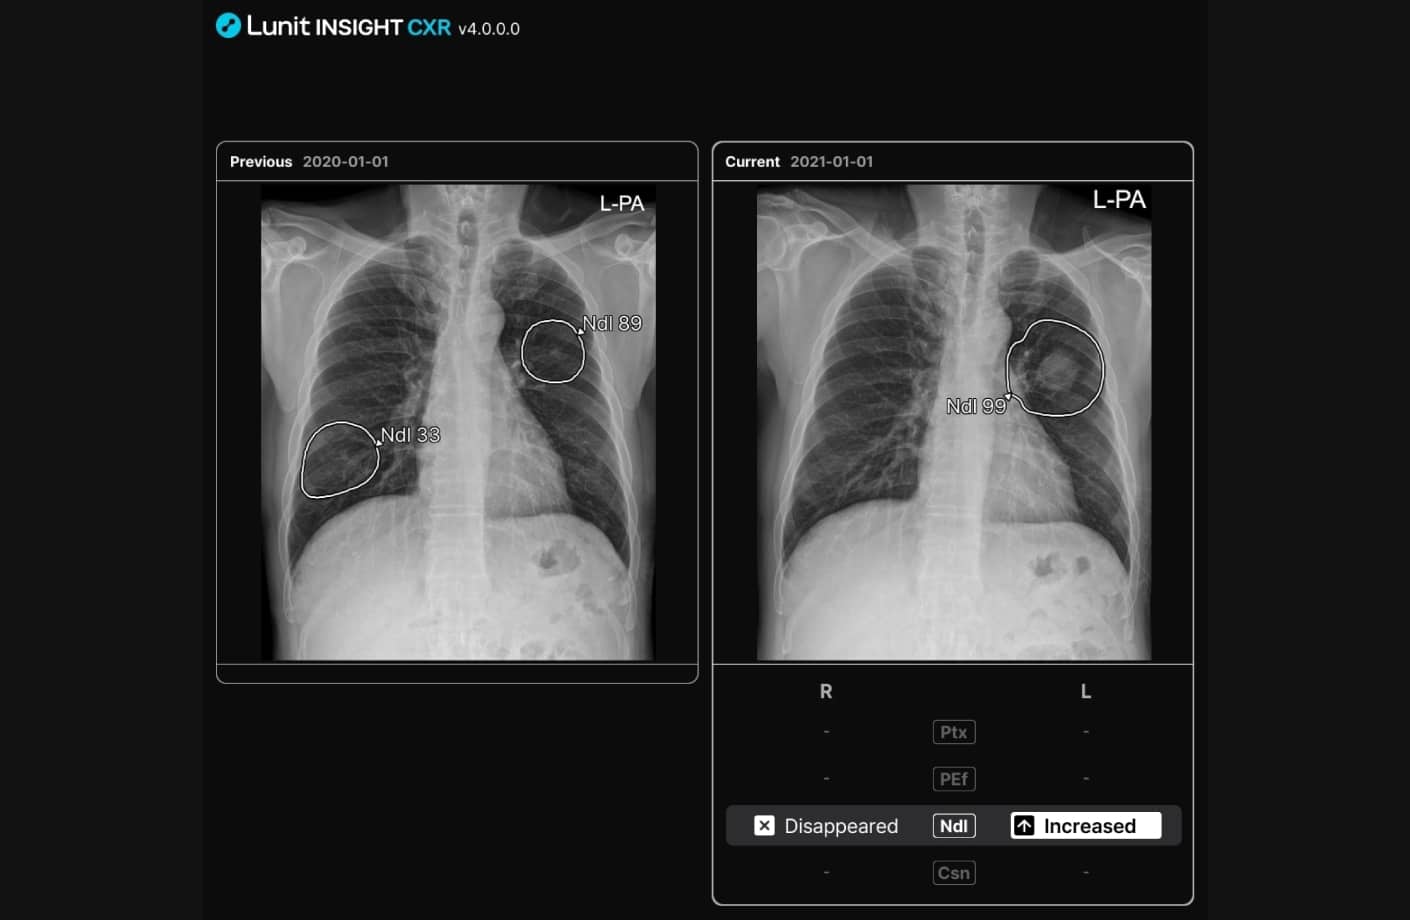

루닛 인사이트 CXR4는 환자의 과거 영상을 자동으로 불러와 현재 영상과 비교해 이상 소견의 변화를 확인할 수 있도록 기호로 표시합니다. 결절의 진행 여부 뿐 아니라 기흉, 흉수, 경화 병변의 면적 변화 추적도 가능합니다.